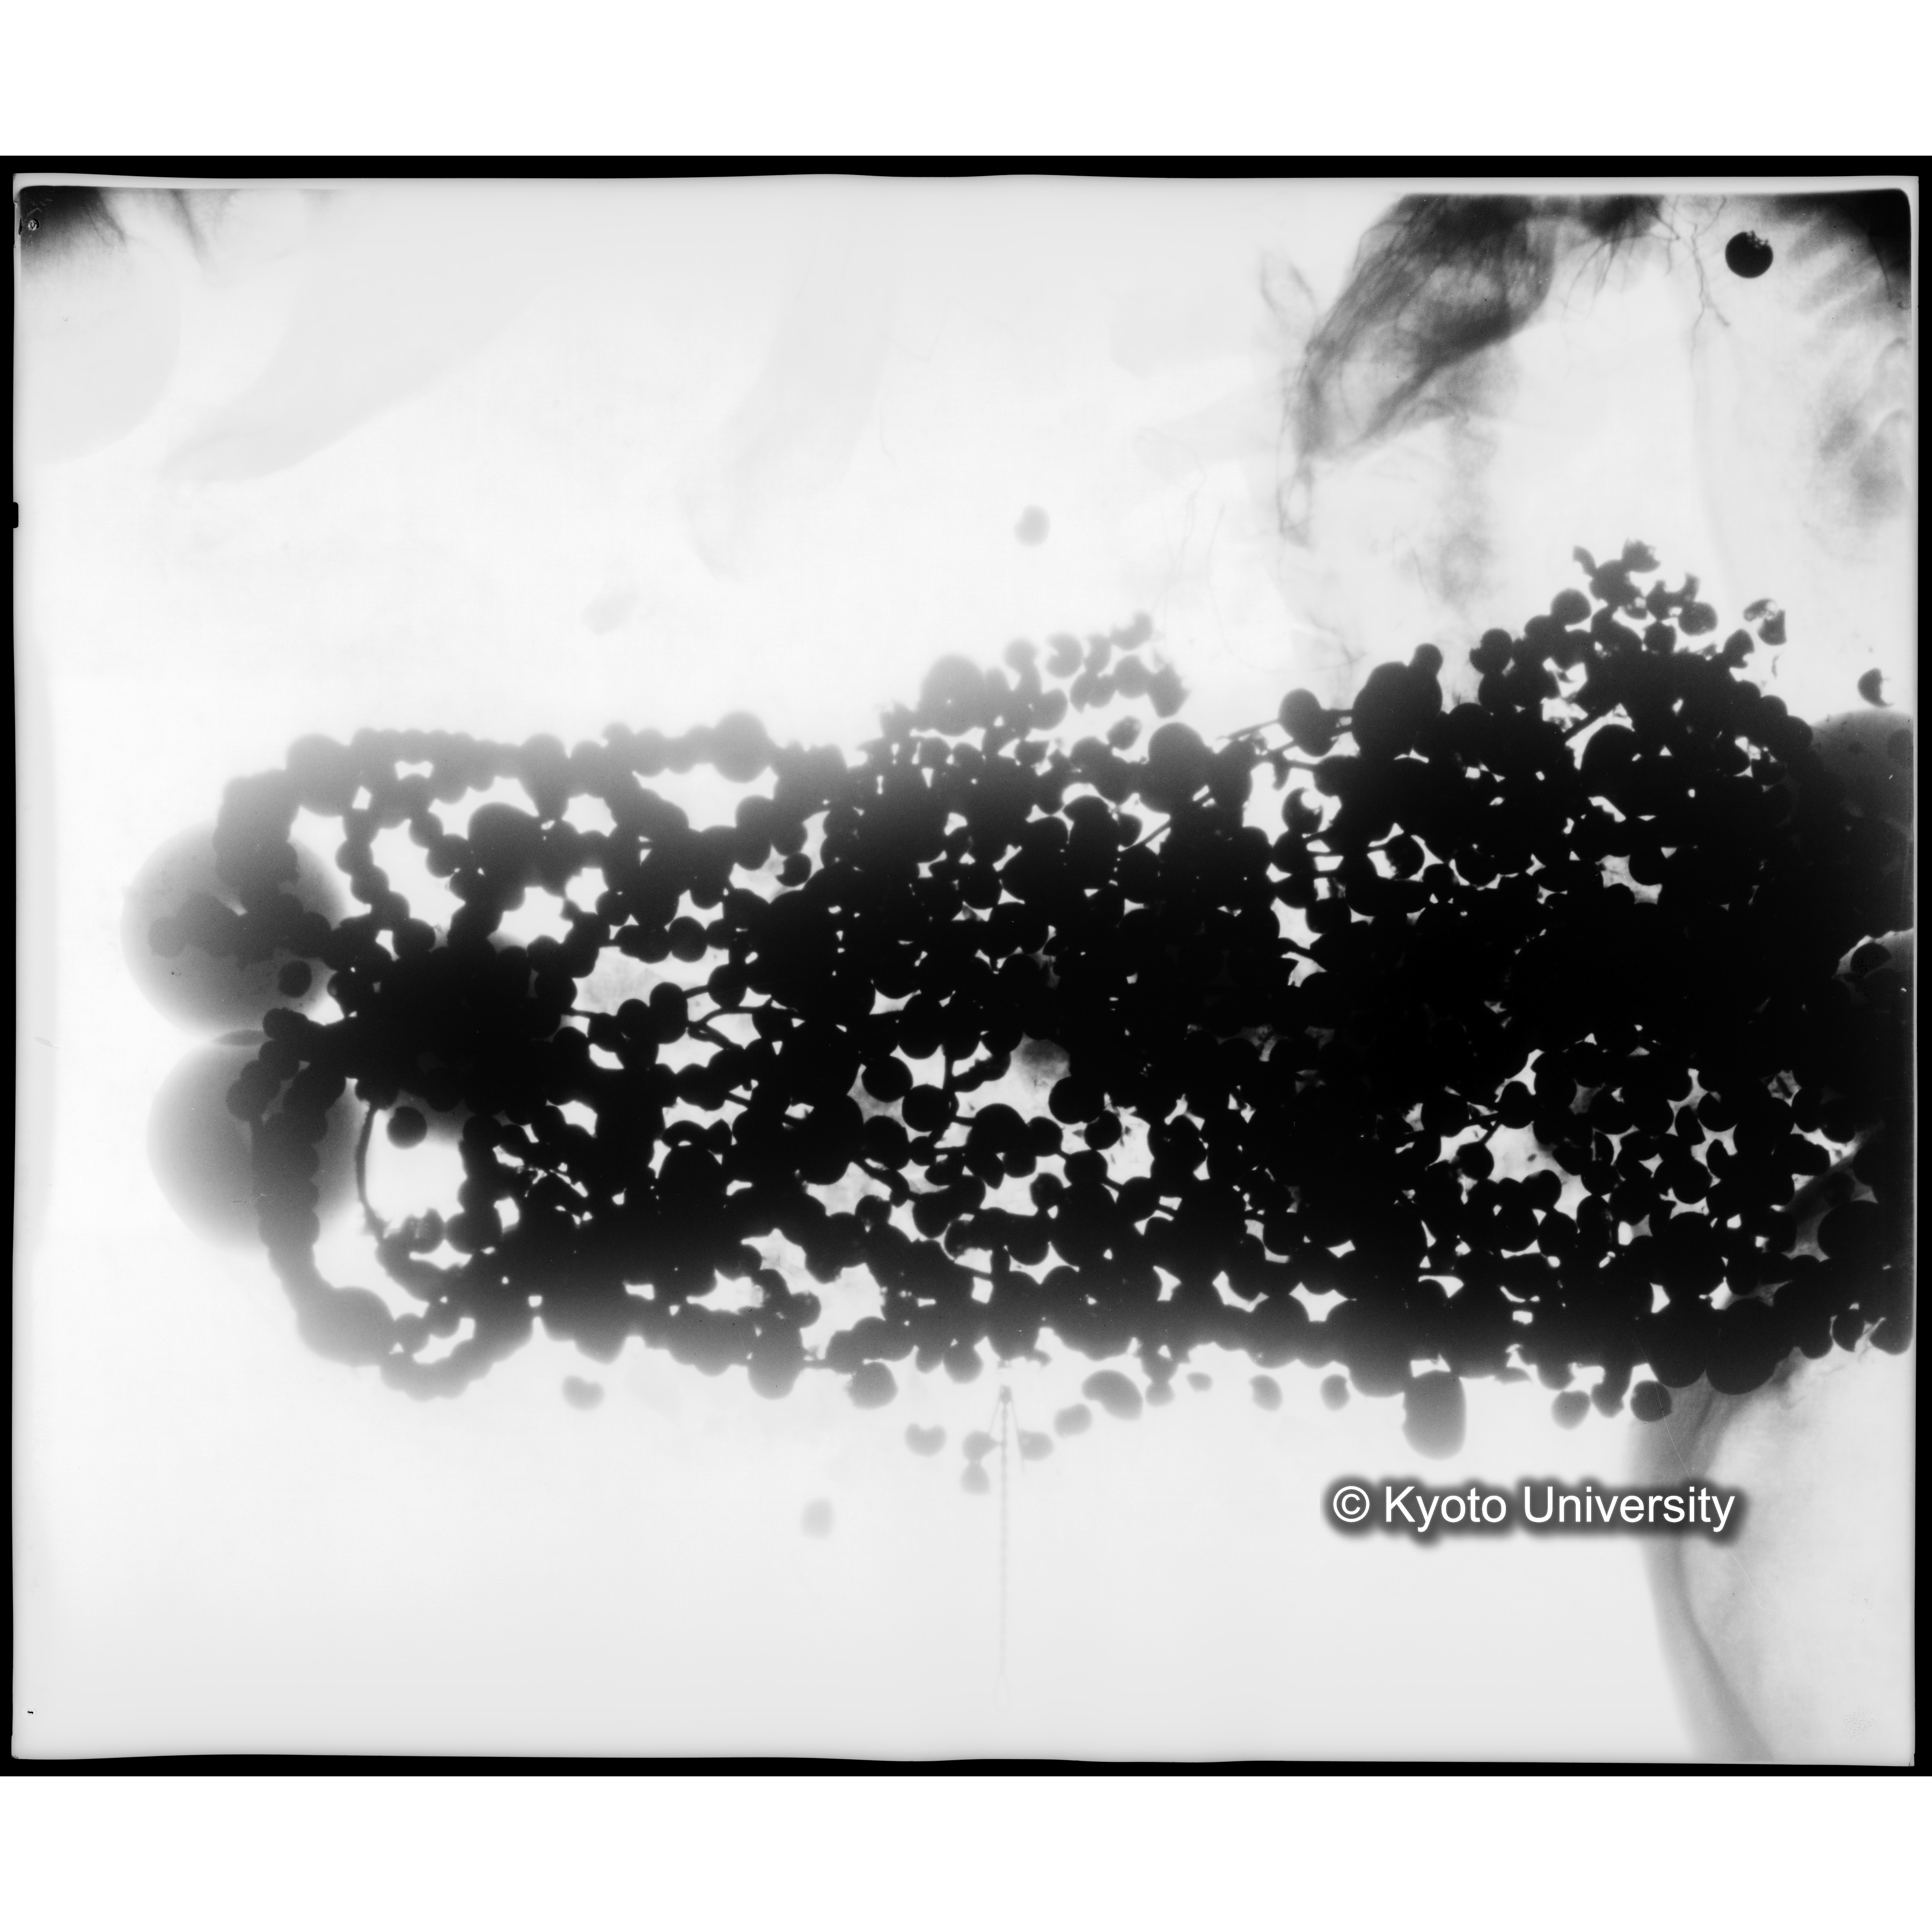

[写真内容] 玉枕レントゲン3

「蘇った古代の木乃伊-藤原鎌足-」における115頁の「43 玉枕 昭和9年6月29日」にコンテンツを反転して右に90度回転したものが対応している. 「蘇った古代の木乃伊-藤原鎌足-」においては一部トリミングがされている.

- 作成: 昭和9年(1934) 6月29日.